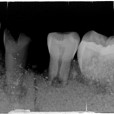

Dit kaakje werd door mijn tandarts grondig bekeken en róntgen foto,s van gemaakt .

Met zijn  langdurige ervaring  uit zijn eigen praktijk. Kunnen namelijk  Molaren verkeerd om zitten. (zie 1ste  molaar linker kaak)

Tevens kunnen er zowel  tanden teveel of te weinig voorkomen .( zie 5 snijtanden ) . De 5de premulaar en hoektand lijken maar een  tand  te zijn , zie rechterkaak. Rontgenfoto wijst echter uit dat het toch 2 aparte tanden zijn .